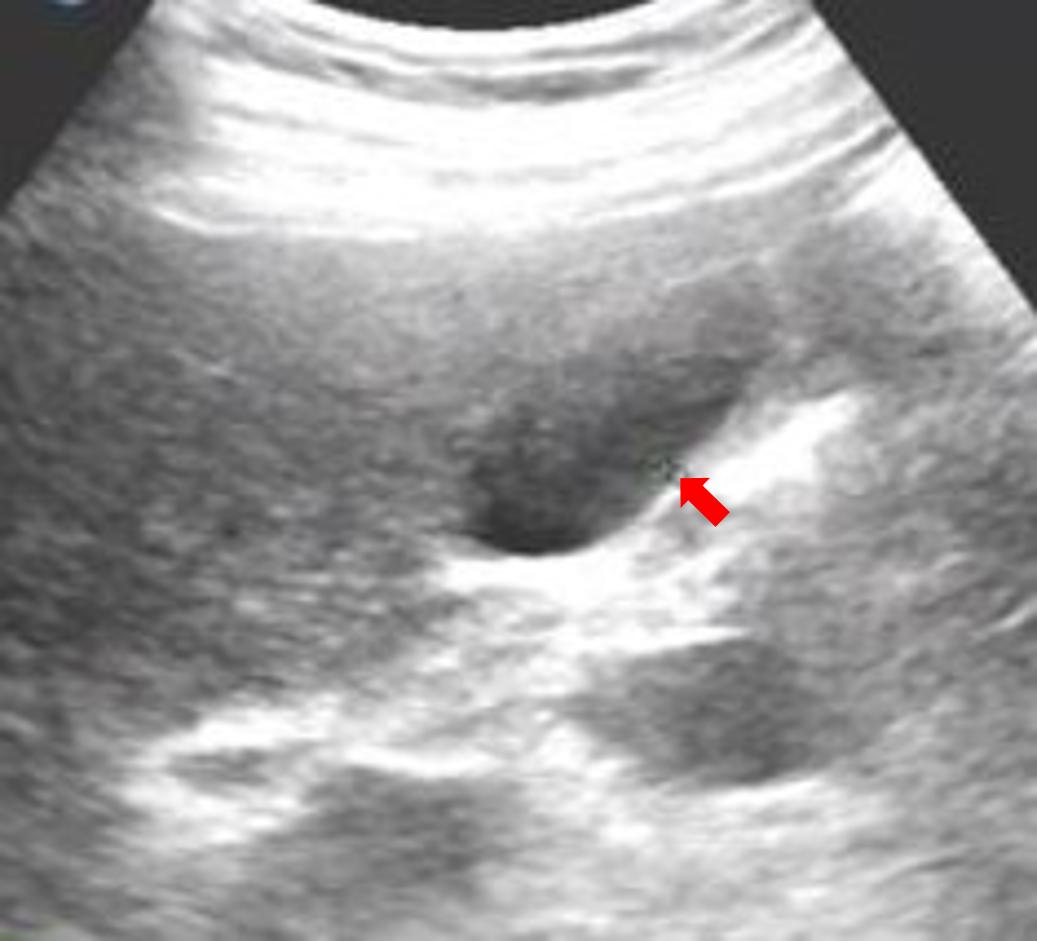

图四,也是空腹患者的胆囊,这种小息肉不到2mm,仔细扫查也可以发现的。

图五,这个红笔圈出的是餐后的胆囊,胆汁排出了一部分,相比之下,这个胆囊壁的褶皱之间有没有息肉和结石,就不好说了。